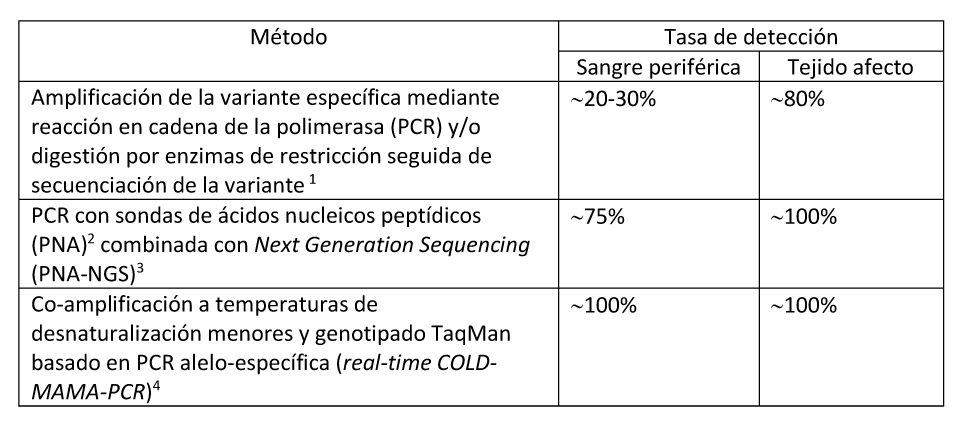

Hay métodos experimentales que se están desarrollando para aumentar la sensibilidad de identificación de las variantes patogénicas e incluso la cuantificación del porcentaje de células mutadas en una muestra (Bianco et al 2000, Narumi et al 2013, de Sanctis et al 2017) (ver Tabla 7). Estos métodos podrían incluso facilitar el diagnóstico en muestras de leucocitos de sangre periférica.

Tabla 7. Técnicas disponibles para la Detección de Variantes Patogénicas en pacientes con Displasia Fibrosa/Síndrome de McCune-Albright

- La capacidad de detección de la variante depende del nivel de mosaicismo en el tejido y de la sensibilidad de la técnica empleada. La tasa de detección más elevada de la variante p.Arg201 usando PCR convencional se da órganos endocrinos, mientras que la más baja se da en muestras de piel. Lumbroso et al 2004, Kalfa et al 2006

- Bianco et al 2000

- Narumi et al 2013

- De Sanctis et al 2017

El análisis mediante métodos basados en la secuenciación por PCR tiene una mayor sensibilidad si se realiza sobre tejido afecto:

- 80% en tejido afecto.

- 20-30% en linfocitos de sangre periférica.

- La detección de variantes patogénicas, es decir de mutaciones, depende del nivel de mosaicismo en el tejido y de la sensibilidad de la técnica. La tasa de identificación de la mutación de GNAS p.Arg201 usando técnicas de PCR estándar es más elevada cuando los tejidos analizados son órganos y menor cuando se realiza sobre especímenes cutáneos (Lumbros et al 2004). La capacidad para detectar mosaicismo afecta la tasa de detección de la técnica (ver Sección de Genética Molecular y Tabla 8).

- Cuando se emplean primers modificados (ácido nucleico peptídico)(Bianco et al 2000) y a su vez se emplea la técnica de Next Generation Sequencing (NGS), la tasa de detección de la variante p.Arg201 es del prácticamente 100% en tejidos afectos y hasta en un 75% en los leucocitos de sangre periférica (Narumi et al 2013).